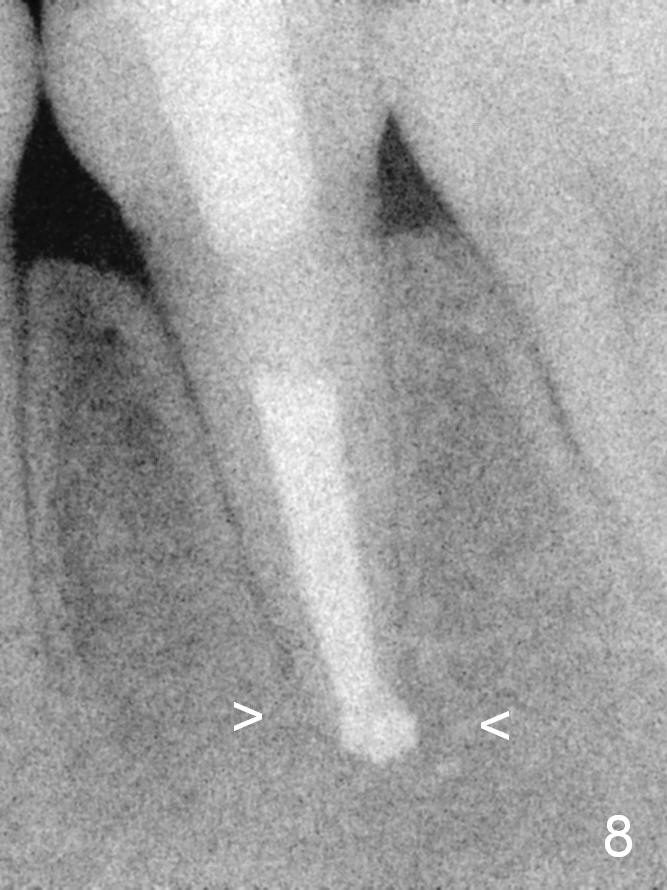

A 13-year-old girl has a buccal apical fistula at the tooth #20 with large periradicular radiolucency (Fig.1 *). After canal debridement, calcium hydroxide paste is placed in the canal (Fig.2 *). One month later, the fistula does not disappear with light percussion. New paste is placed (Fig.3). Two months later, the fistula disappears without percussion. The existing paste (Fig.4) is changed (Fig.5 (yellow: radiolucency; red: Inferior Alveolar Canal)). Another 2 months later, the fistula does not recur; as before, the paste density decreases, so does periradicular radiolucency (Fig.6). Root canal is packed (Fig.7). Six months postop, periradicular radiolucency continues to decrease, while the lamina dura at the apex is discontinuous (Fig.8 between arrowheads). Seven years postop, the lamina dura at the apex is seemingly intact (Fig.9). The patient remains asymptomatic at #20. In fact there is an acute infection at #29.